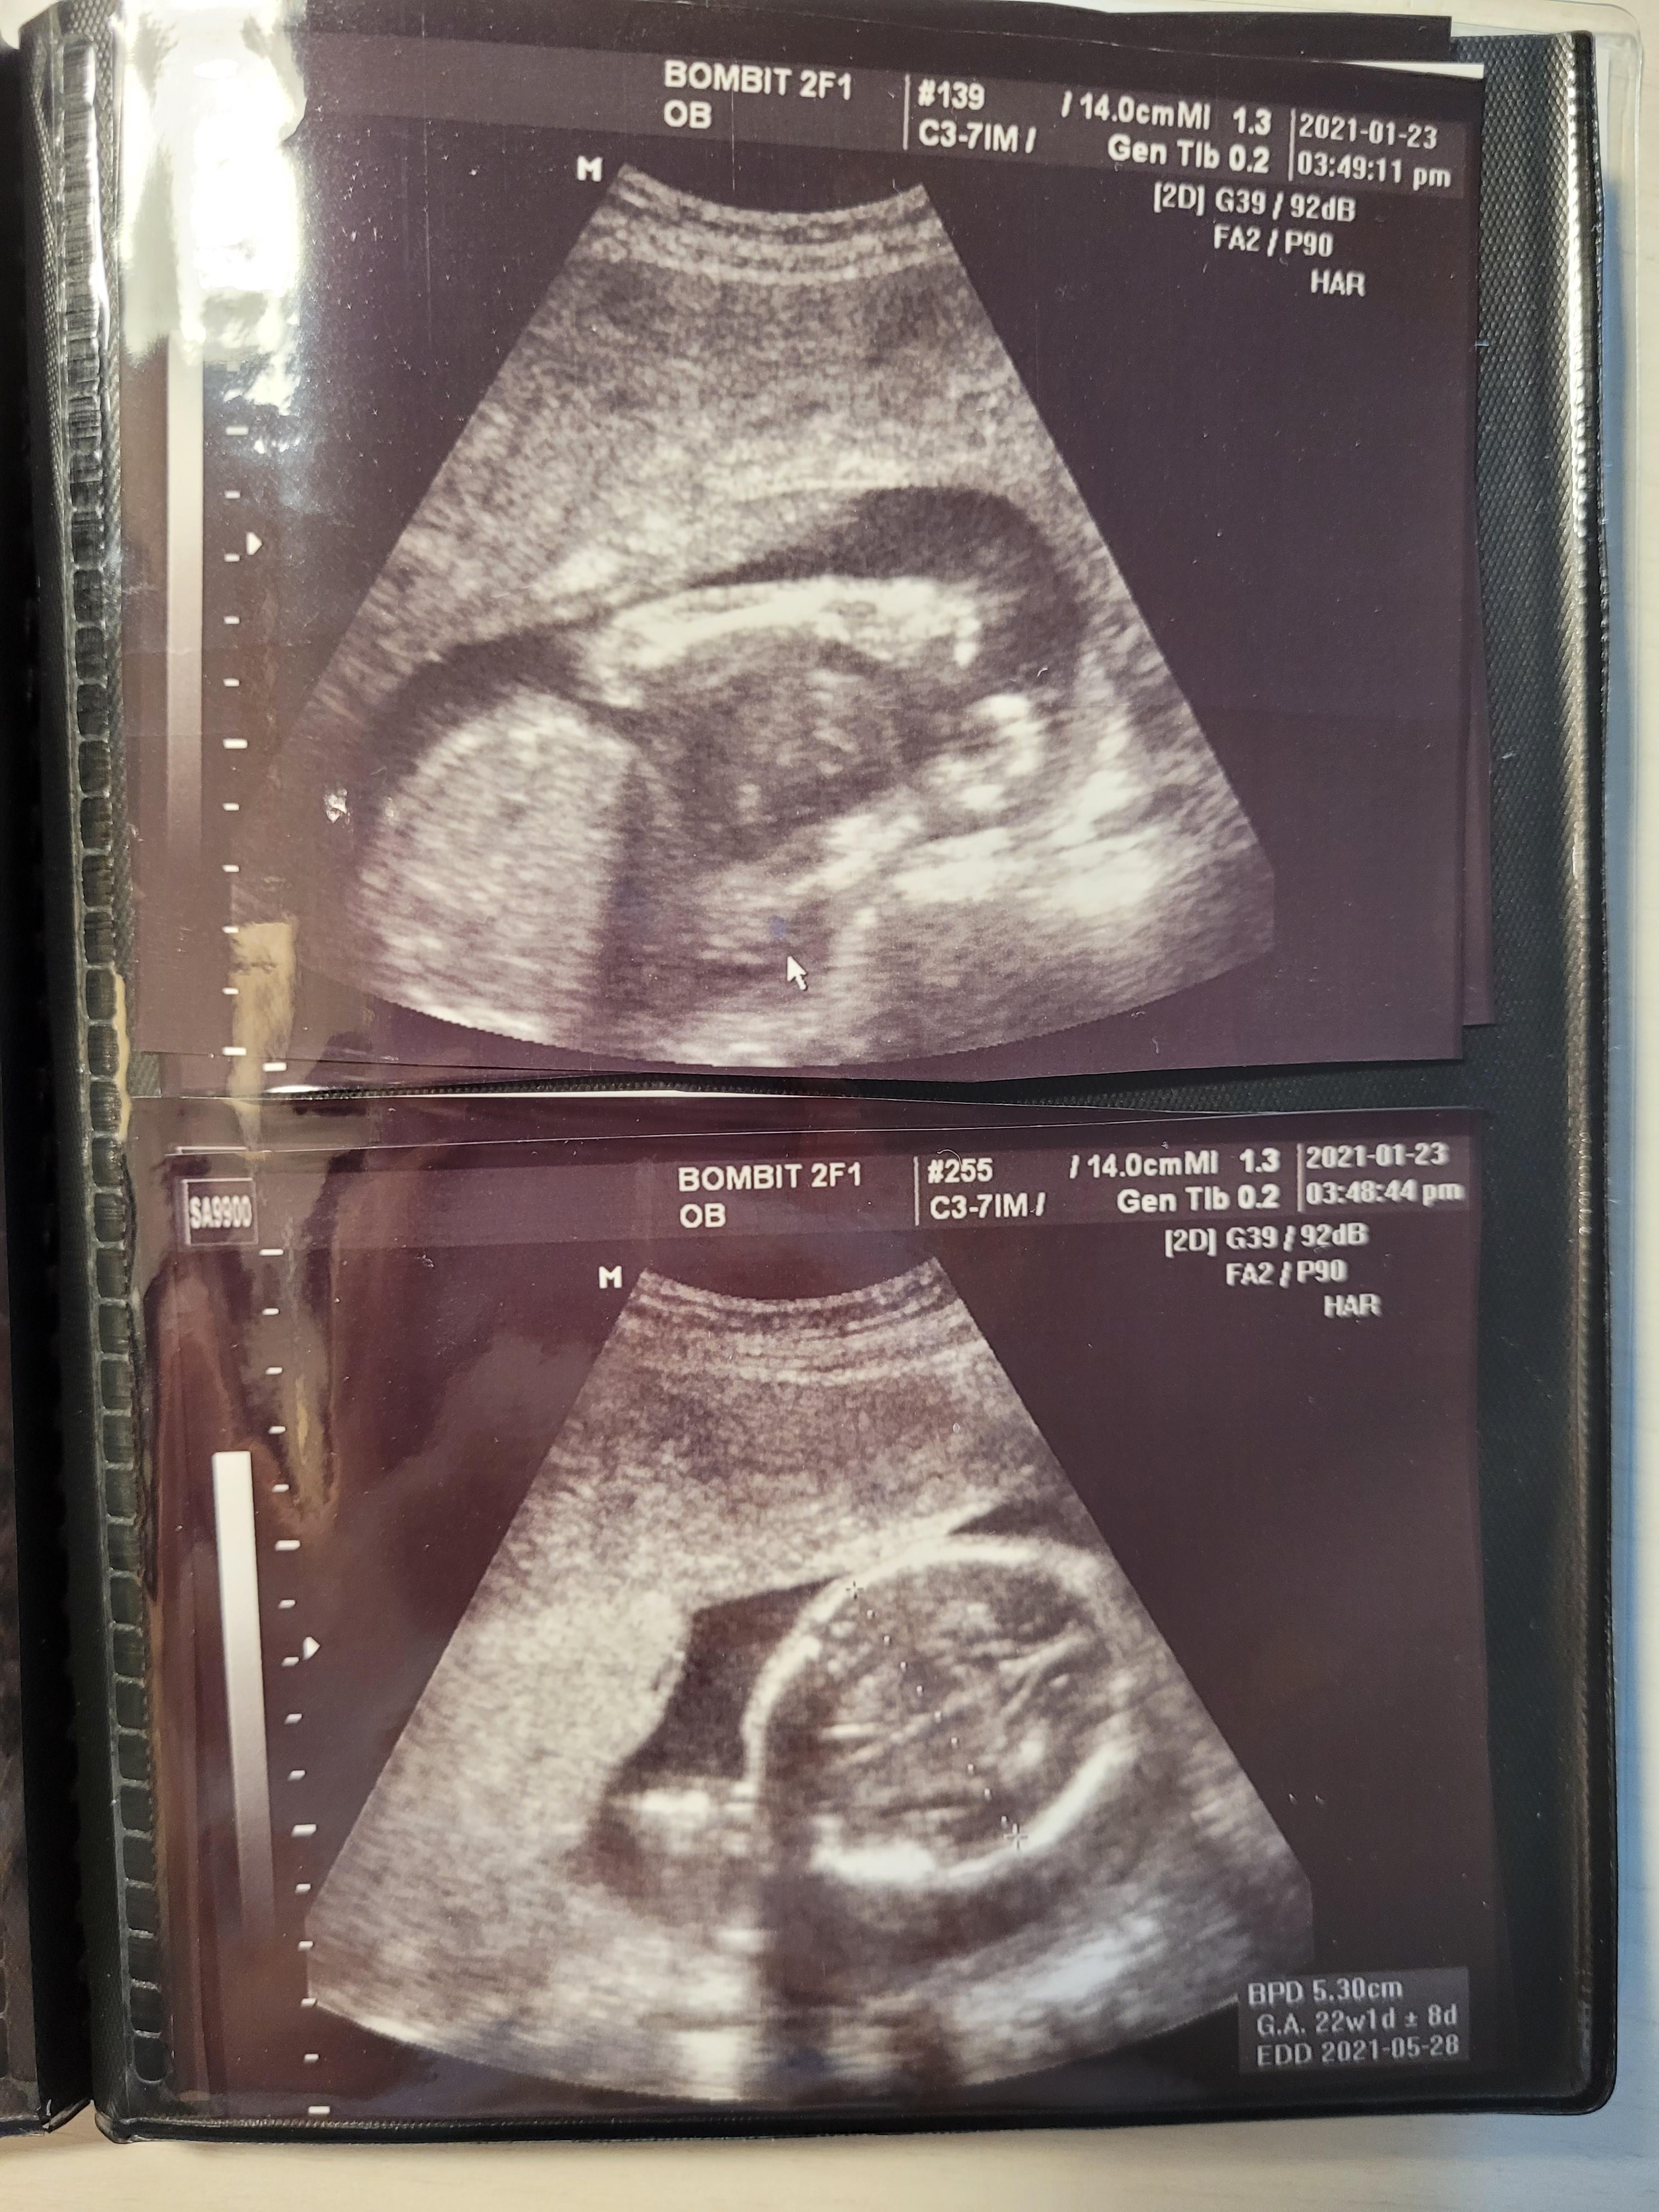

임신 20주 정밀초음파 / 봄빛병원 정밀초음파 후기

20주가되서 정기검진일이에요.

봄빛병원에서는 20주에 정밀초음파를 보는데요.

주치의 진료실이 아닌, 정밀초음파실에서 꼼꼼하게 20~30분정도 보는 초음파에요.

접수 후, 바로 정밀초음파실로 가서 정밀초음파를 먼저 보고,

다시 주치의선생님 진료와 일반초음파검사를 합니다.

20주였는데, 22주 주수로 자란 행복이에요.

머리부터 시작해서 발끝까지 정말 꼼꼼하게 봐주십니다.

손발, 눈코입은 물론이고요. 뇌초음파, 동맥 등등 혈관, 양수량, 척추 등등

20분정도 꼼꼼히 봐주셨어요.

사진을 다 올리기엔 너무 많을 정도로 꼼꼼히 봐주셨어요.

사진도 엄청 많이 뽑아주셨어요.